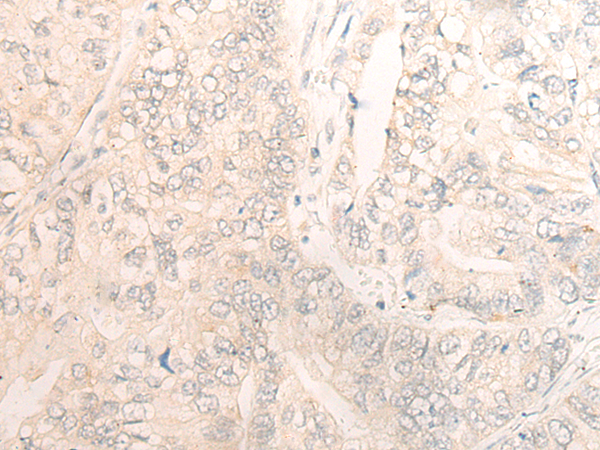

分类: 科研抗体货号: P13262别名: DMN; SYN应用: IHC反应种属: Human